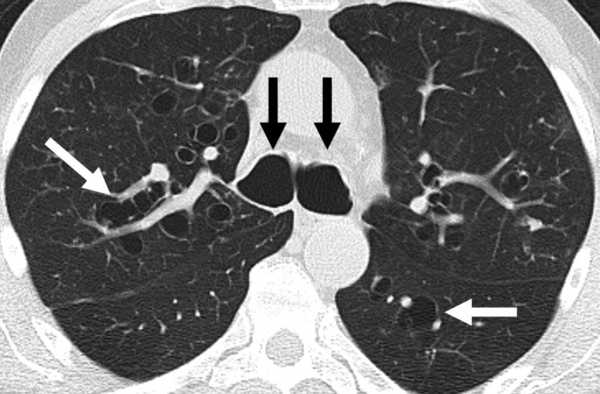

По словам специалиста, на флюорографии тяжелее всего увидеть центральный рак. В эпикризе Ирины Д. также указано, что у нее именно центральный рак правого верхнедолевого бронха с множественными метастазами обоих легких.

— Центральный рак исходит из крупных бронхов, а тень крупных бронхов может прятаться за тенью сердца или накладываться на тень сердца на рентгенограмме и флюорограмме. Это от врачей не зависит, потому что у каждого метода диагностики есть свои достоинства и недостатки. На той же флюорографии периферический рак легких лучше виден, так как он расположен больше к периферии легких.

- При центральном росте на рентген — снимке определяется уплотнение корня легкого и расширения его размера, возможна визуализация тени опухоли и признаки бронхиальной непроходимости – ателектаз сегмента или доли легкого.

- Периферический рост характеризуется тенью опухоли различного диаметра и любой локализации в пределах легочных полей.

Трудности заключаются в том, что на ФЛГ центральную опухоль трудно заметить в прямой проекции, только по изменению интенсивности тени, увеличению ее размера и изменению структуры корня можно предположить наличие опухоль.

Периферический рак, локализованный в нижней доле правого легкого так же затруднителен для диагностики, так как в прямой проекции пульмональные поля перекрывает тень печени.

- Центральный рост – на снимке видно уплотнение и расширение лёгочного корня, также не исключена возможность определения затемнения, которое указывает на наличие опухоли, визуальные симптомы непроходимости бронх — ателектаз (безвоздушность лёгочной ткани, характеризующаяся спаданием альвеол в определённой области либо во всём лёгком).

В прямой проекции сложно обнаружить центральную опухоль, её присутствие можно заподозрить только по наличию тени, а также по изменению структуры тканей.

- Периферический рост – отличается тенью новообразования различной величины, которые расположены в пределах лёгочного органа.

Флюорография при раке лёгких периферической формы, которая расположена на нижней части правого лёгкого, в прямой проекции также сложно обнаружить, так как её часто закрывает тень печени.